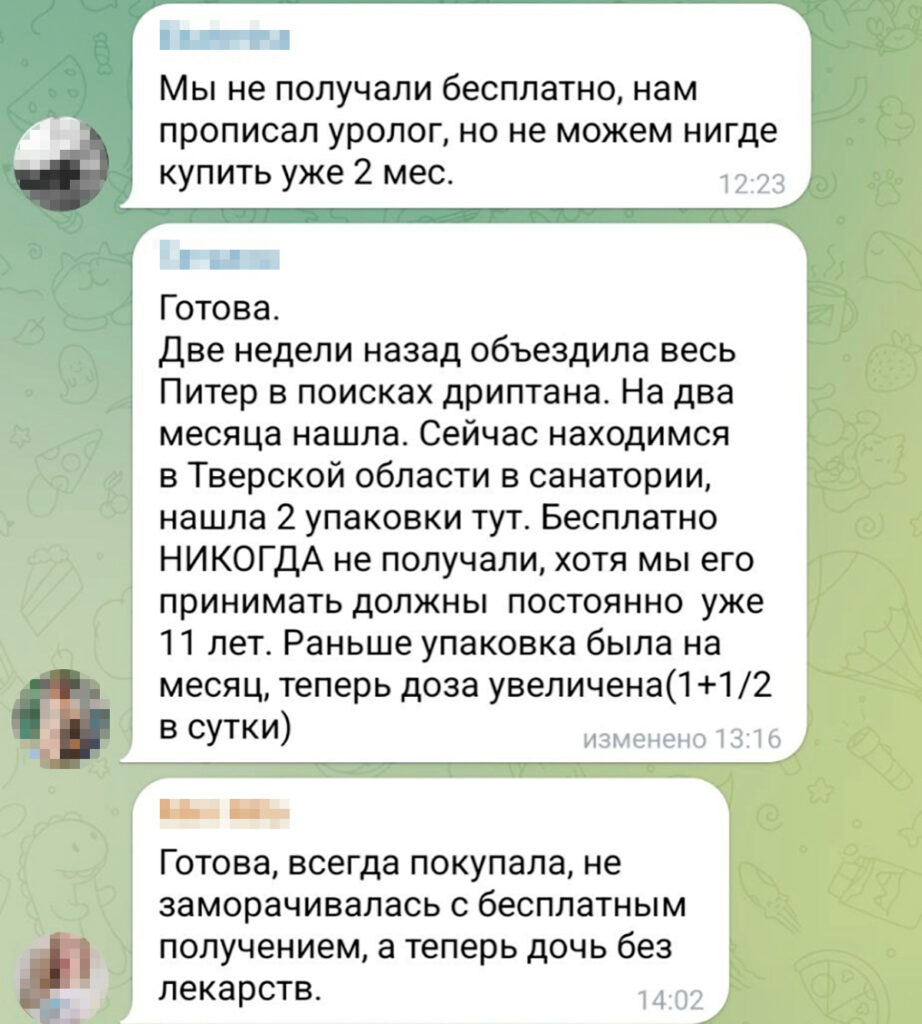

Оксибутинин (действующее вещество препарата Дриптан) принимают для уменьшения количества мочеиспусканий и снижения давления — это обеспечивает нормальное развитие и работу мочевого пузыря и почек ребёнка. Таблетки нужно принимать постоянно, длительное время — до тех пор, пока сохраняются симптомы, пояснил «Вёрстке» Артём Бершадский. В ряде случаев симптомы сохраняются в течение всей жизни. Поэтому сообщество родителей детей со Spina bifida забеспокоилось, и когда препарат начал пропадать из российских аптек, они начали массово обращаться в фонд «Спина бифида», который помогает детям с одноименным диагнозом. Отсутствие препарата в аптеках обсуждается и в комментариях к публикациям фонда в «Телеграме».